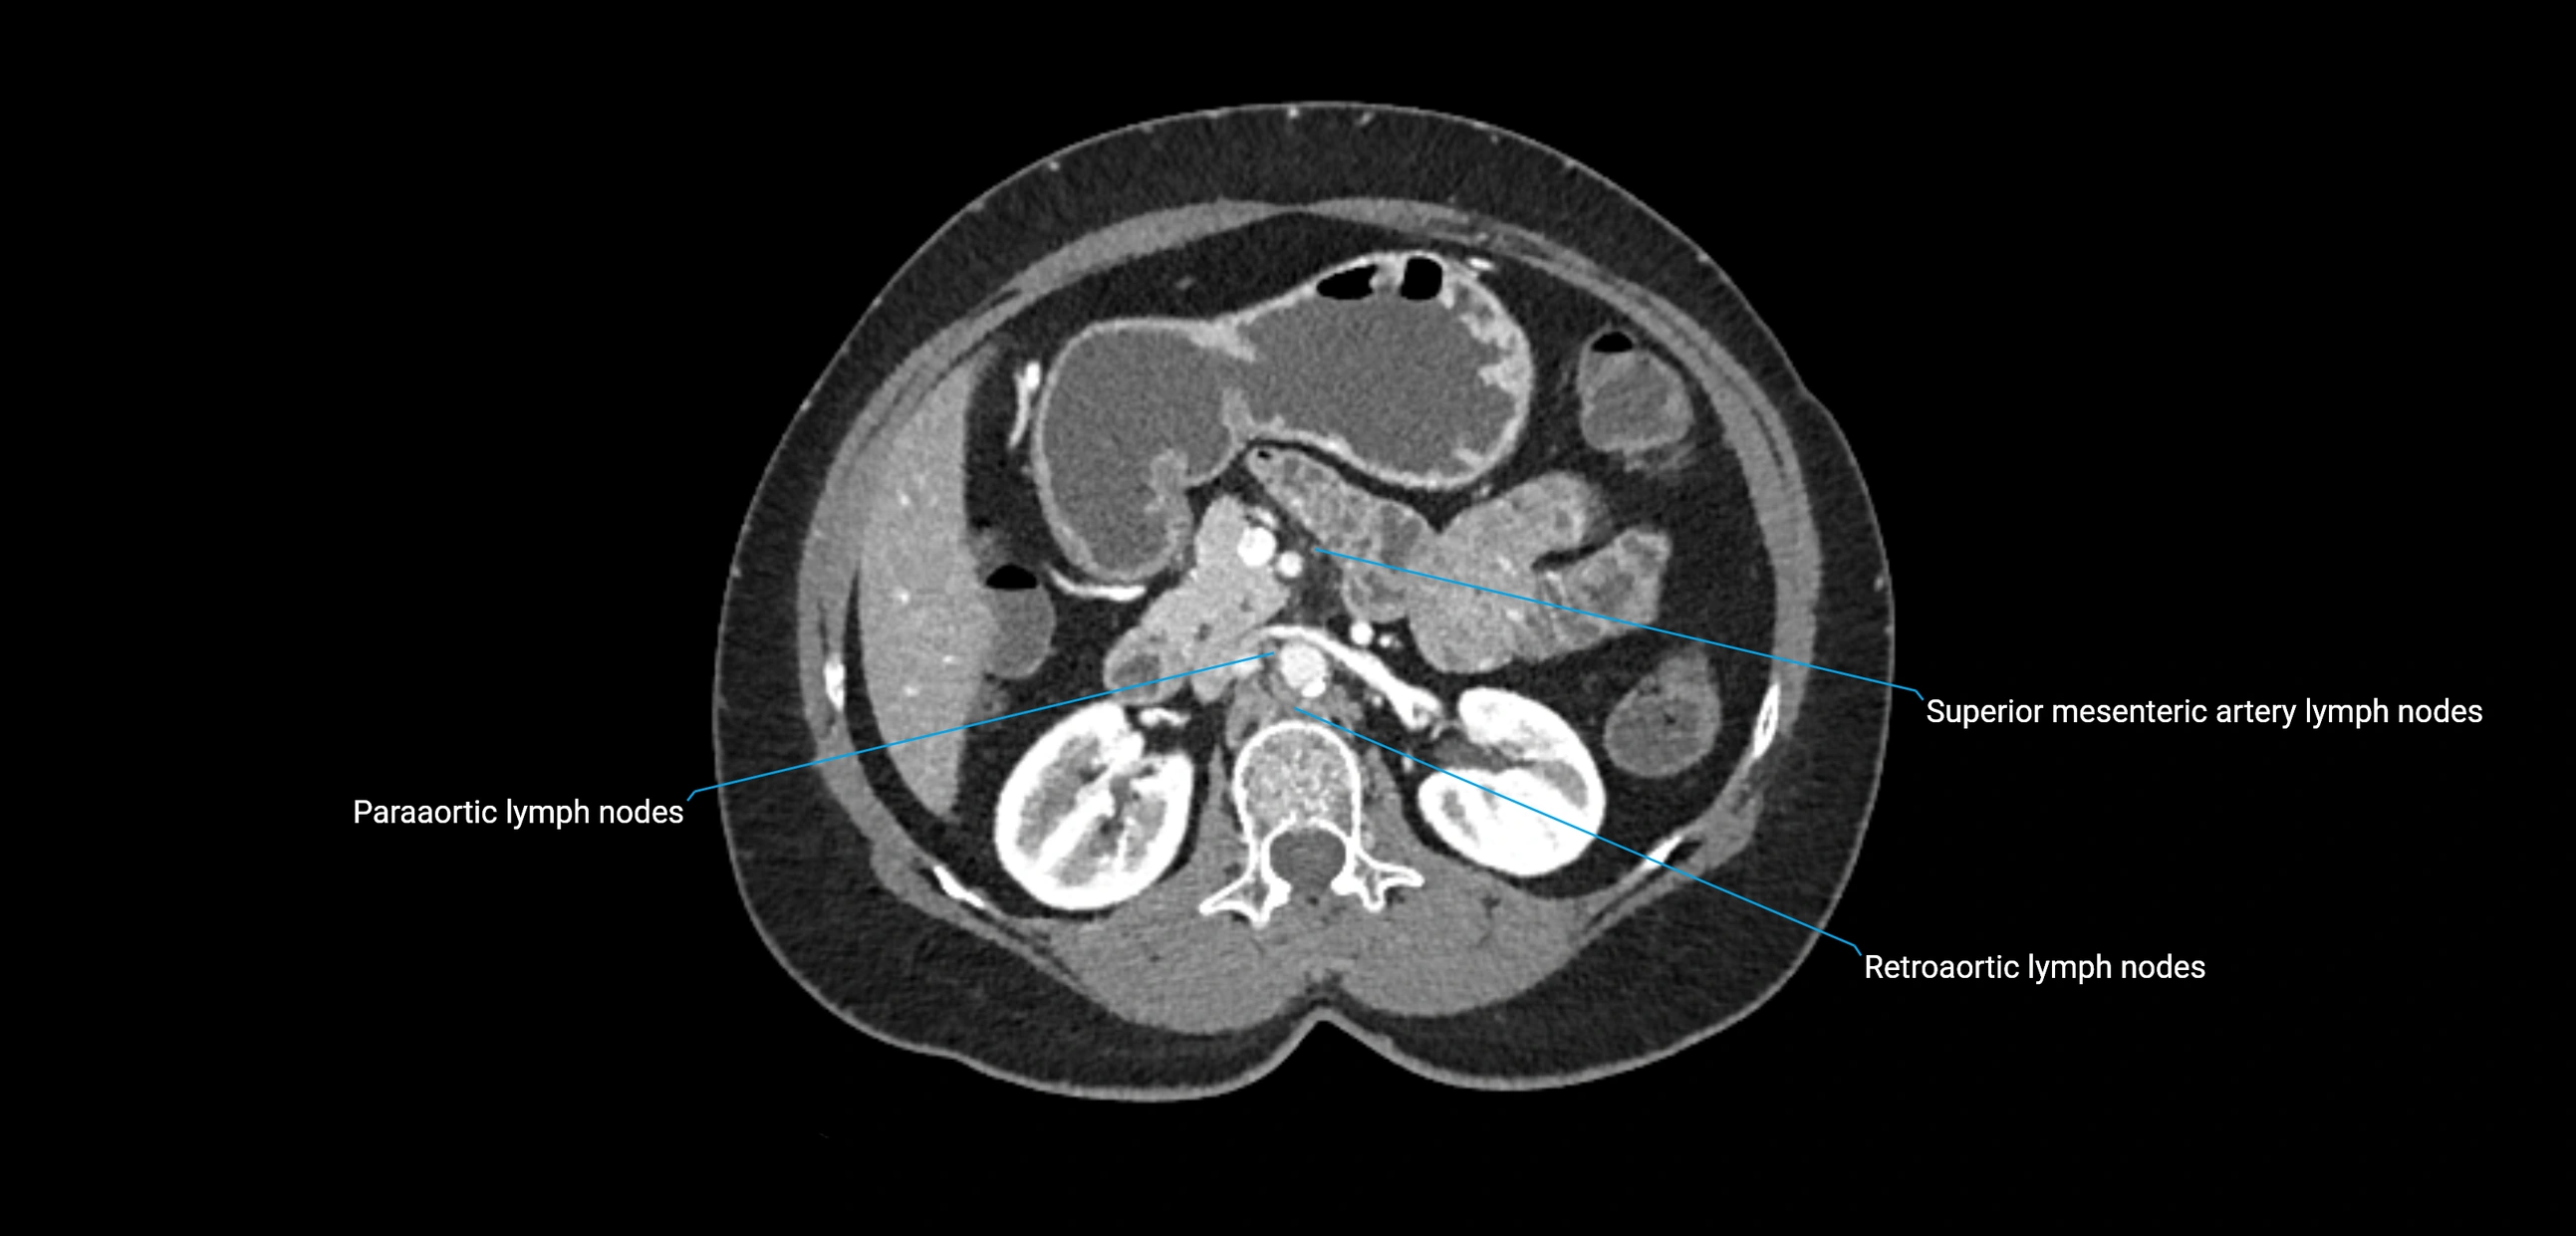

CT Appearance

CT Pre-Contrast:

• Nodes appear as soft-tissue density nodules adjacent to the aorta and IVC

CT Post-Contrast:

• Normal nodes enhance homogeneously

• Malignant nodes may show heterogeneous enhancement, central necrosis, or conglomerate formation

• Size >1 cm short axis is suspicious, though morphology and distribution are equally important

CT image

image